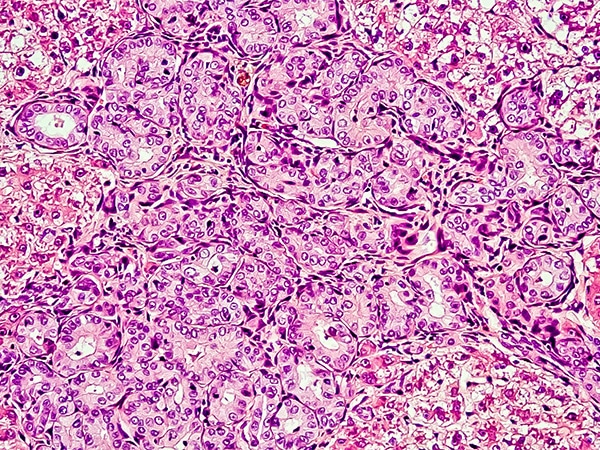

As a result of the new approval, pembrolizumab can now be used for treating patients with hepatocellular carcinoma — the most common form of primary liver cancer diagnosed in the United States — that has progressed despite treatment with the molecularly targeted therapeutic sorafenib (Nexavar). Sorafenib has been the standard first treatment for patients diagnosed with advanced hepatocellular carcinoma since it was first approved by the FDA in 2007.